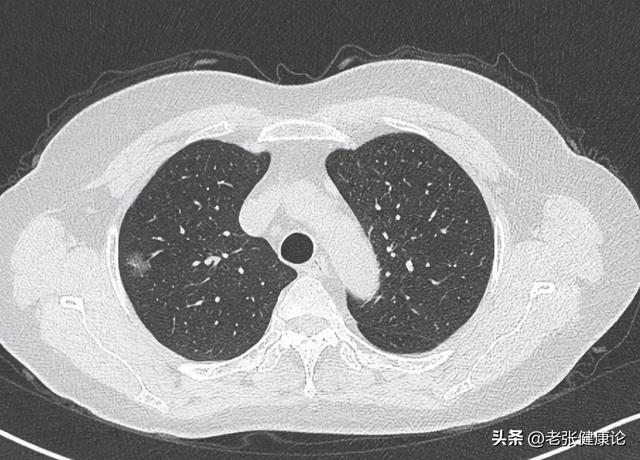

“大夫,我爸前两天刚作念完肺癌手术,今天非要吃一大盘腊肉,还说‘补一补’。”在门诊里十大正规体育平台app,阿琴一边说,一边悄悄抹眼泪。她父亲老赵,65岁,老烟民,查出肺癌早期,好抑遏易作念了手术。